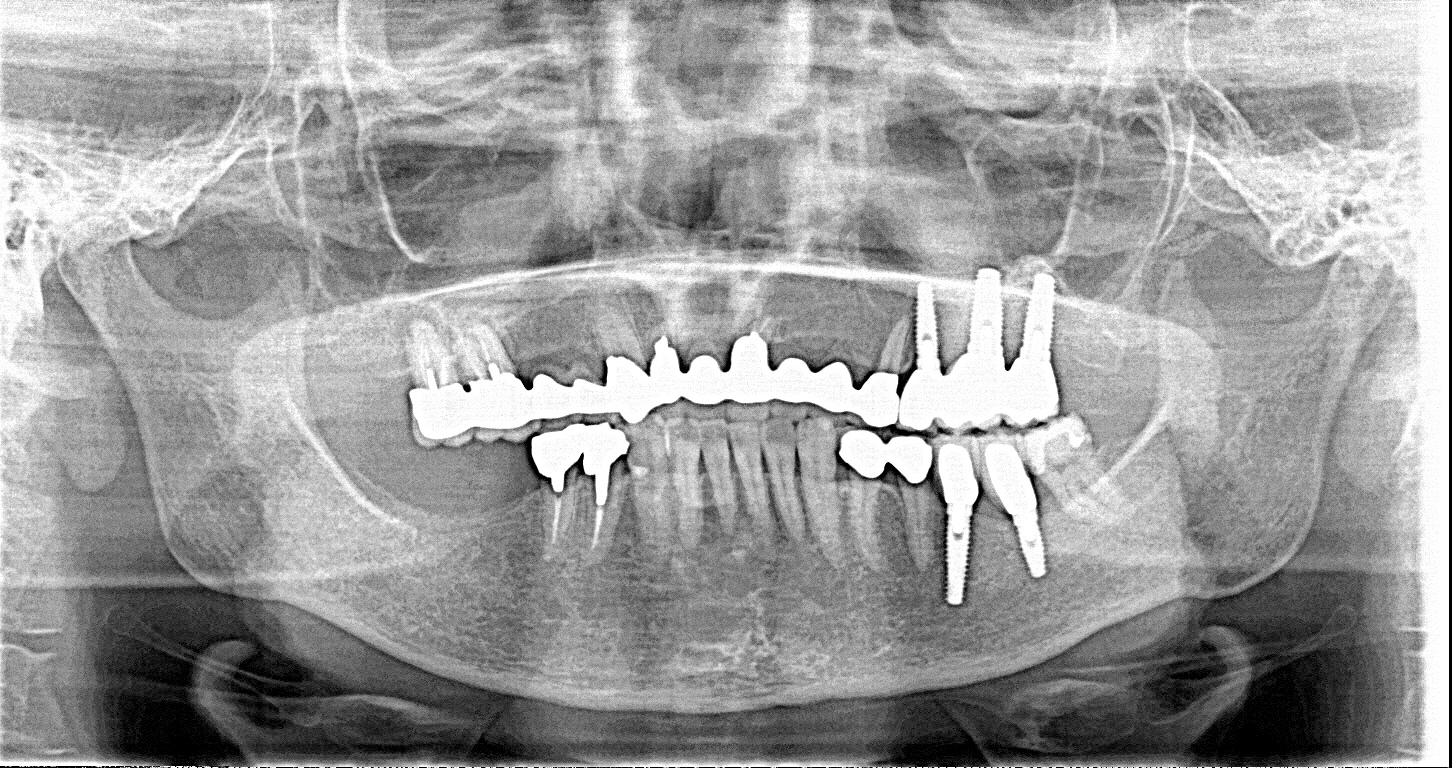

この患者様は、右上の奥歯の歯茎から出血してくるとのことで来院されました。歯周組織検査とレントゲンで診断を行った結果、重度の歯槽膿漏が認められ、保存不可能の為、抜歯になると伝えたところ、入れ歯は絶対に嫌だと言われたので、インプラント治療となりました。CT撮影を行ったところ、上顎洞底までの距離が3ミリ程度しかなかったのですが、骨が固く、フィクスチャーの一次固定が良好だったので、開窓法による上顎洞底挙上術とフィクスチャーの埋入を同時に行いました。約10カ月後に二次手術を行い、上部構造をセットしました。また、右下の臼歯部のブリッジにも大きな二次カリエスが認められ、7番の遠心根が抜歯になり、6番、7番にインプラント治療をしました。